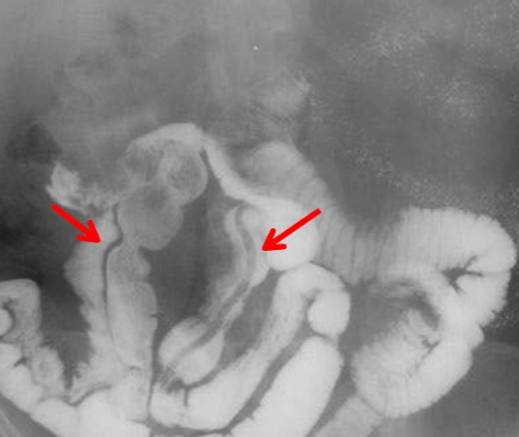

Иногда червя удается обнаружить во время проведения контрастной рентгенографии тонкого кишечника. Он имеет вид светлых полос.Что касается общего анализа крови, то в нем можно обнаружить увеличение числа эозинофилов, лейкопению и анемию. Однако эти показатели являются проходящими.